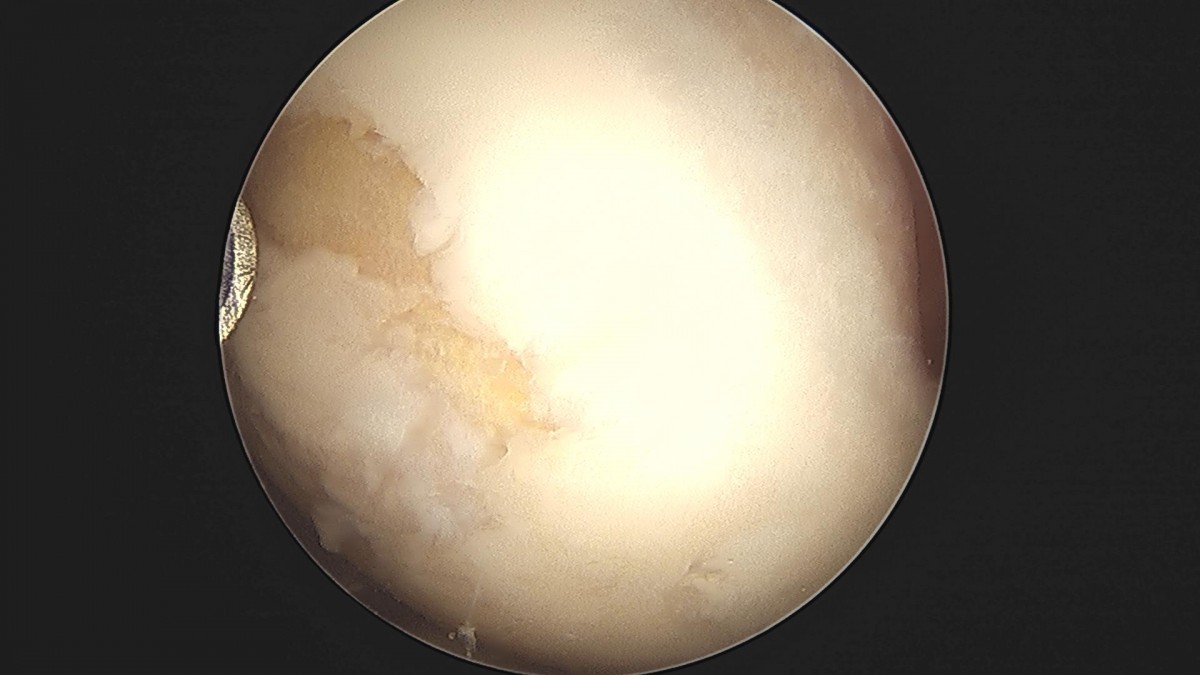

배우한원장님 무릎 반월상연골판 절제술 박대O 환자

작성자 최고관리자 댓글 0건 조회 2,233회 작성일 23-01-12 18:00